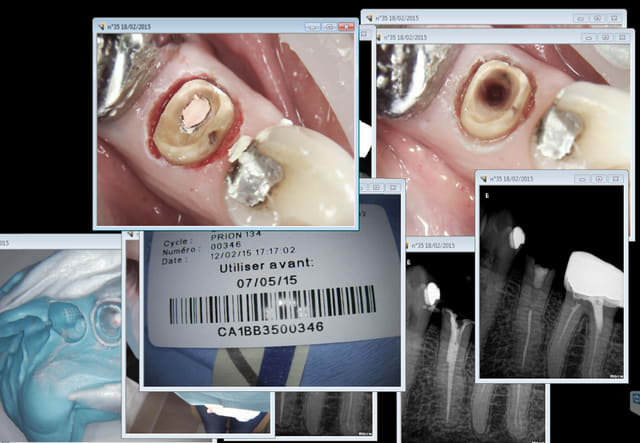

A nouveau patiente qui paie 800 euros par an (1600 euros pour le couple) sa mutuelle qui ne rembourse meme pas une couronne métal, pas un centime à investir dans une reconstitution pré-endo ni dans une dés-obturation canalaire. on fait avec les moyens du bord pour bosser au sec.

RTE taille empreinte 40 mn. (une merveille ce R25 en dés-obturation, comme si le tt canalaire n'existait pas)

Systématiquement j'enregistre le "contexte" avec toutes les images et radios concernant l'acte, notamment la tracabilité sté. ca m'évitera de me prendre la tete si un jour enquiquineur de bureaucrate me demande des justifications.